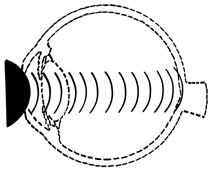

ANTERIOR–POSTERIOR COMPRESSION AND EQUATORIAL EXPANSION

The volume of a closed space cannot be changed. Therefore, when the eye is compressed along its anterior–posterior axis, it must either expand in its equatorial plane (Fig. 3) or rupture. Using high-speed photography, Delori and associates27 studied blunt trauma in enucleated pig eyes. The cornea was indented 8.5 mm, reducing the original anterior–posterior axis by 41% and bringing the posterior surface of the cornea into contact with the iris and the lens. The equatorial plane was expanded to 128% of its original length. Specific examples of damage caused by this severe stretching of the ocular tissues are discussed later.

FIG. 3. When the eye is compressed along its anterior-posterior axis, it expands in its equatorial plane (small arrows), causing severe traction at the vitreous base (large arrows).